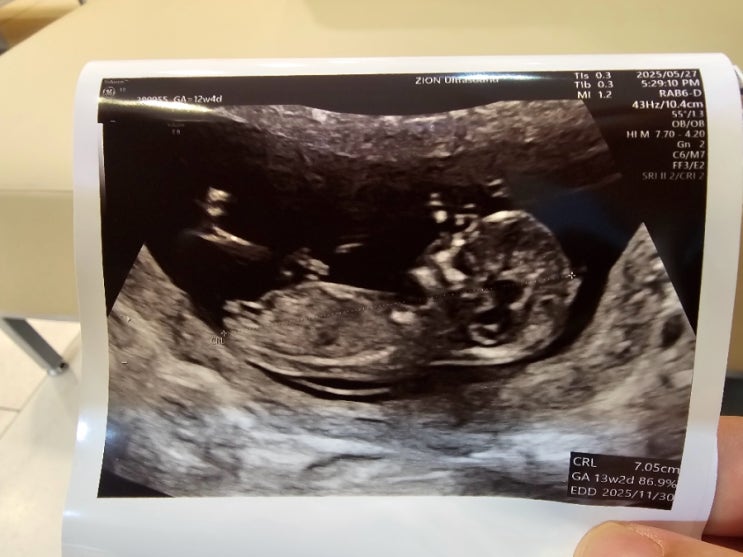

수원 시온 여성병원 임신 13주 차 초음파 검사

어느덧 튼튼이가 벌써 13주 차가 되었습니다. 산부인과에 한 번 들러봅니다. 임신 12주 차 즈음부터 1차 기...